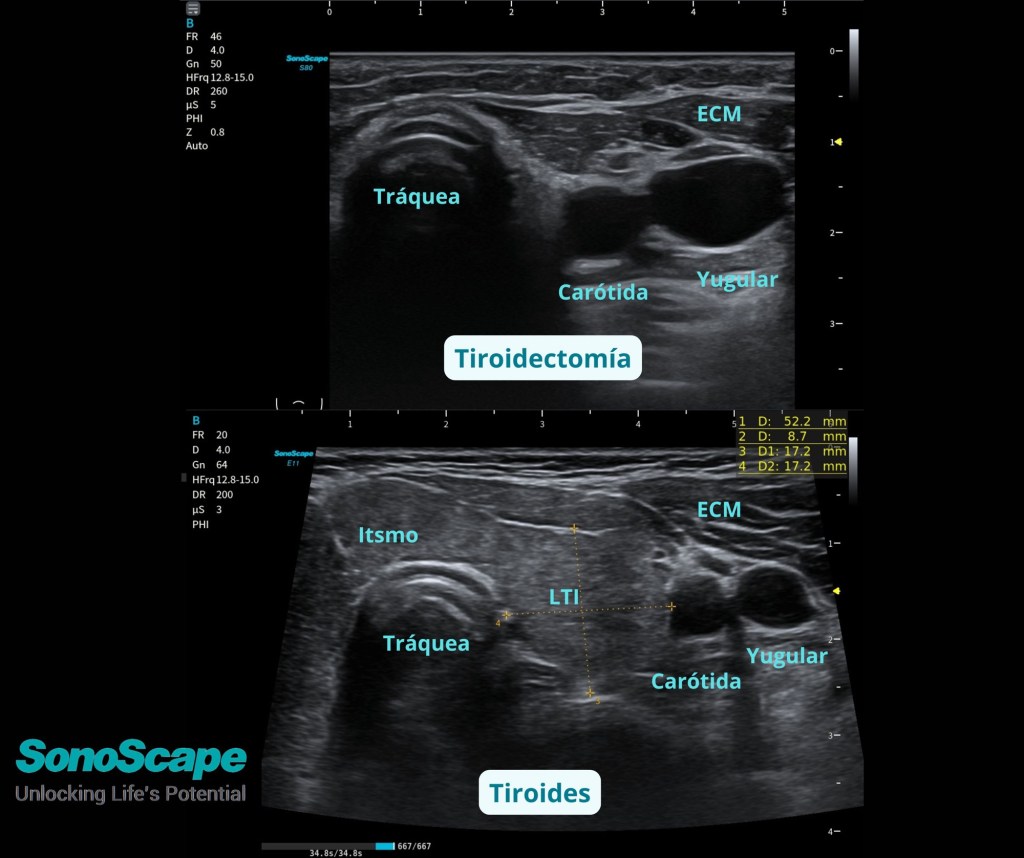

Ecografía de cuello: Tiroidectomía

En la #Imagen #Superior vemos un cuello tras #Tiroidectomía total 👉 la glándula ha sido extirpada.

En la #Imagen Inferior, #Tiroides está presente (un poco globuloso), con su #Istmo y lóbulo izquierdo (#LTI) identificable.